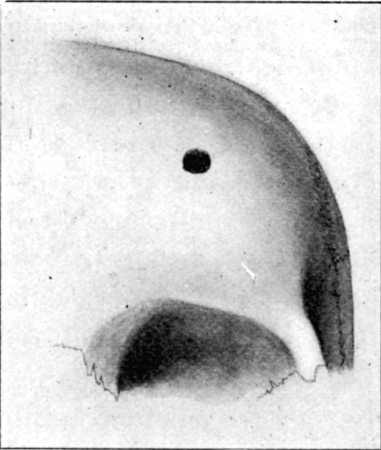

1. Section of Mauser Aperture of Entry To face p. 73

2. Section of Mauser Aperture of Exit 76

25a. Sections of Mauser Entry and Exit Wounds74